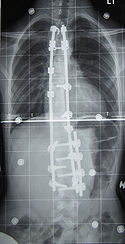

Stage 4: Once the disc height progresses to the point that the vertebrae are touching or nearly touching, we have entered stage 4. By this time the disc is largely dried out and either dead or nearly dead. The bone spurs which have been forming can become an increasing problem if they project posteriorly where the nerves exit the spinal canal. If they grow large enough they run the risk of of hitting the nerves and causing symptoms of nerve pain or numbness.

Stage 5: Once the vertebrae have been grinding against each other, bone on bone, further changes take place. In the cervical vertebrae the touching vertebrae often fuse forming 1 bone. In the thoracic and lumbar spine this usually does not occur due to the pressure on the joint from the body weight above this level. Instead, the bones will deform forming odd joints and shapes.